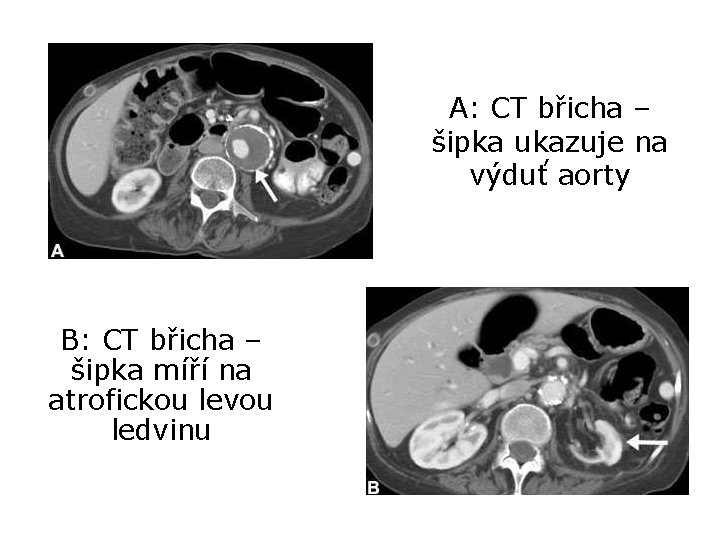

Kazuistika 2 • 60 ti-letá pacientka přivezena s rychle se rozvíjející paraplegií a kompletní anestézií dolní poloviny těla • v osobní anamnéze má operaci výdutě břišní aorty Které dráhy jsou postiženy? O jak rozsáhlé postižení míchy „na příčném řezu“ se jedná? Jaká by mohla být příčina náhlé paraplegie?

Výsledky vyšetření MR T-L páteře ischémie u T 5 + konus

A: CT břicha – šipka ukazuje na výduť aorty B: CT břicha – šipka míří na atrofickou levou ledvinu